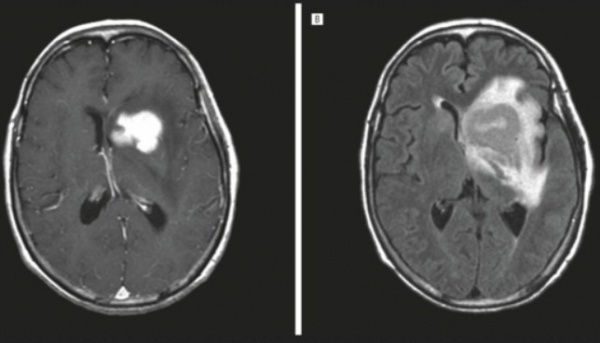

- Нейровизуализация. Церебральная КТ или МРТ позволяют оценить размер и расположение новообразования, степень дислокации серединных структур. В пользу лимфомы ЦНС говорит многоочаговость процесса, кольцевидное контрастирование, значительный перифокальный отек.

Дифференцировка осуществляется по характерным особенностям МРТ. Для глиобластомы типичны некротические очаги центральной локализации, отсутствующие у лимфомы. С целью исключения метастатического характера новообразования производится поиск первичной опухоли экстраневральной локализации. Церебральный абсцесс характеризуется четким контуром. Лимфому ЦНС следует также отличать от нейросаркоидоза, лейкоэнцефалопатии, демиелинизирующих заболеваний, в пользу которых будет свидетельствовать диффузно-многоочаговый характер поражения.